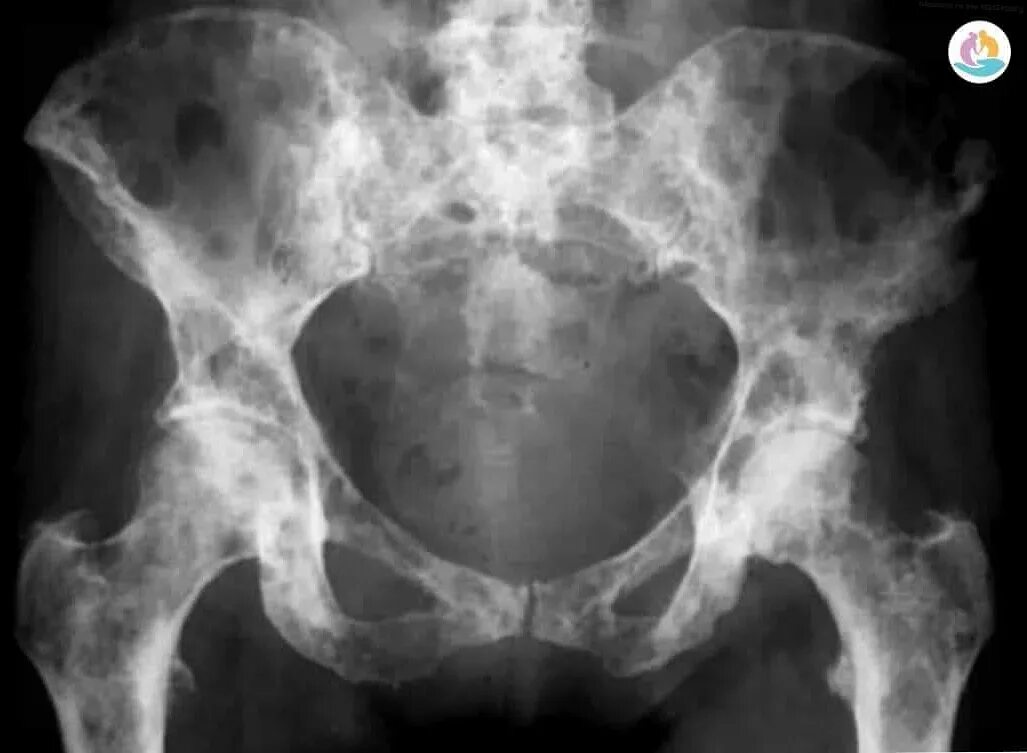

Метастазы в тазу